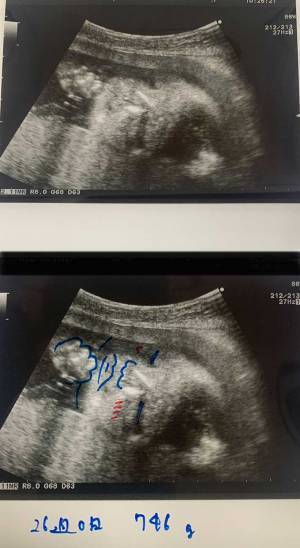

「エコー写真は見慣れていない人が見ると、どこが顔や身体なのかが分からなくなることがあると思うので、帰ってから困らないように、片方に絵を描いて渡しています」

今井さんは2枚のエコー写真を出し、そのうちの1枚にどこが顔や身体なのかが分かるよう、絵を描いているのだとか。

こんなふうに、線をなぞってイラスト化されていたら、とても分かりやすいですね!

今井さんが赤いペンで足しているほっぺたによって、よりかわいらしさが増して見えますね…!